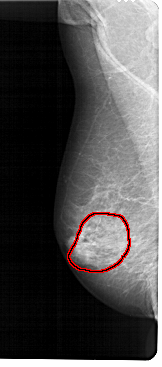

RIGHT_MLO LINES 5386 PIXELS_PER_LINE 2461 BITS_PER_PIXEL 12 RESOLUTION 43.5 OVERLAY

FILE: A_1302_1.RIGHT_MLO.OVERLAY

TOTAL_ABNORMALITIES 1

ABNORMALITY 1

LESION_TYPE CALCIFICATION TYPE PUNCTATE-AMORPHOUS DISTRIBUTION REGIONAL

ASSESSMENT 4

SUBTLETY 3

PATHOLOGY BENIGN

TOTAL_OUTLINES 1

BOUNDARY